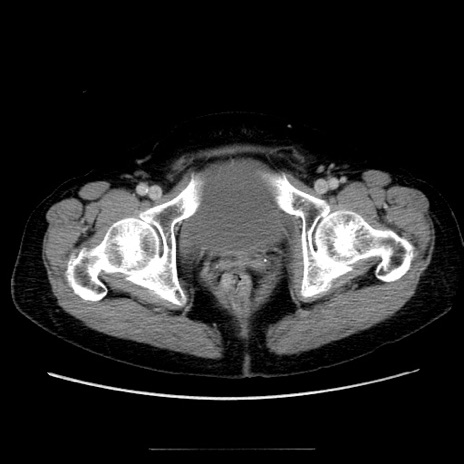

冠状断像

【症例】70歳代女性

【主訴】お腹が張る

【現病歴】1週間くらい前から腹部膨満の自覚あり。昨日夜から増悪したため、本日救急外来受診。

【身体所見】意識清明、BT 36.5℃、BP 165/106mmHg、HR 80bpm、SpO2 98%、腹部:膨満、軟、自発痛・圧痛なし、触診にて不快感あり、腸蠕動音:減弱

【データ】WBC 12600、CRP 1.04